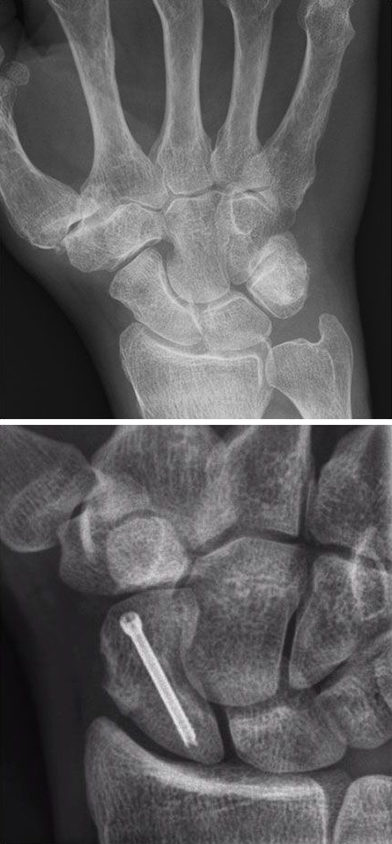

Versorgte Kahnbeinfraktur, Mittelhandknochenfraktur

Fracture de l'os scaphoïde, fracture du métacarpe

La fracture est une fracture osseuse, qui peut intervenir à un ou plusieurs endroits de l’os, avec ou sans déplacement (dislocation) de fragments osseux.

Les fractures de la main, resp. des doigts, comptent parmi les fractures osseuses les plus fréquentes et la fracture du radius distal (fracture du poignet) est celle qui survient le plus souvent chez l’homme. Selon l’importance du déplacement osseux et si une articulation est touchée, une stabilisation chirurgicale peut être nécessaire. En fonction du type de fracture, elle se fera à l’aide de vis et/ou de plaques, ou par coelioscopie, en insérant câble metallique ou vis via de toutes petites incisions.